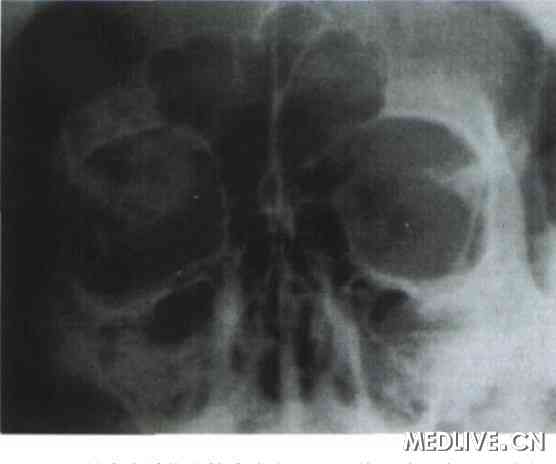

例1

患者男性,48岁,因左眼球突出伴视力下降1年1988年8月30日入院。体检: 全身情况无特殊。眼部检查:裸眼视力右眼0.9,不能矫正;左眼0.1,戴+ 1.00 DS矫正至0.3。双眼晶状体皮质轻度混浊,眼底检查示左眼后极部包括黄斑区有放射状脉络膜皱褶,右眼底无特殊表现。眼球突出度:右眼12 mm,左眼16mm, 眶距100mm,眶缘触不到肿物,双眼正位,眼球运动正常。眼底荧光素血管造影检查:提示左眼后极部条纹状高荧光,符合脉络膜皱褶。A型超声波检查提示: 左眶颞侧球后有一中高波反射,实性占位性病变波形。眼眶X线平片提示左眼眶上部见一高密度组织影,密度不均,呈细网状,边界清楚(图1)。CT检查示左眼眶外侧壁蝶骨大翼处见一软组织块影,大小为2.1cm×1.8 cm,CT值55~65 Hu, 左蝶骨大翼骨质呈膨胀性改变,骨质不规则增厚并向周围膨胀,左眼球向前内移位,眼环正常,无骨质破坏(图2)。入院诊断:(1) 左眼眶肿物;(2) 双眼老年性白内障初发期;(3)左眼屈光不正。于1988年9月4日在局部麻醉下行左眼外下方穹隆部结膜切口+外眦部皮肤切开前路开眶肿物摘除术,术中见外侧眶内有一3. 0 cm×2. 5 cm×1. 5 cm紫红色肿物,锥形,边界清楚,触之易出血,肿物与外侧骨壁相连,且相连处骨质增生,将肿物连同增生骨质切除后见骨壁呈蜂窝状改变,用骨蜡填充骨壁缺损后分层缝合。术后组织病理学诊断为:左眼眶蝶骨内海绵状血管瘤。术后6个月复查:右眼视力0.9,不能矫正,左眼视力0.3,不能矫正;眼球突出度:右眼12 mm,左眼13 mm;眶距100 mm,双眼正位,眼球运动正常。

图1 眼眶骨内海绵状血管瘤患者眼眶X线平片示左眼眶上部见一高密度组织影,密度不均,呈细网状,边界清楚